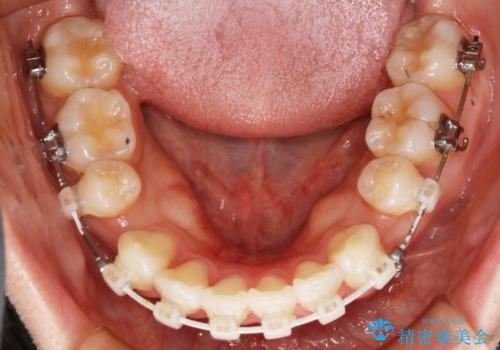

- ワイヤー(片顎舌側装置)

- 歯のガタつきと出っ歯感を治したいとの主訴でご来院され、ハーフリンガル装置を希望なさったため、検査を行ったうえで上下左右4番目の歯を抜歯し歯列を内側に引っ込めつつ叢生の改善を行うこととなりました。

ハーフリンガル装置

ハーフリンガルとは上顎を裏側、下顎を表側のワイヤー装置で治療する場合をいいます。

フルリンガル(上下とも裏側)で治療するよりも費用が抑えられ、治療期間も伸びにくい傾向にあります。また、下顎の舌側に装置がないおかげで口内炎や発音障害もフルリンガルに比べて少ないとされています。